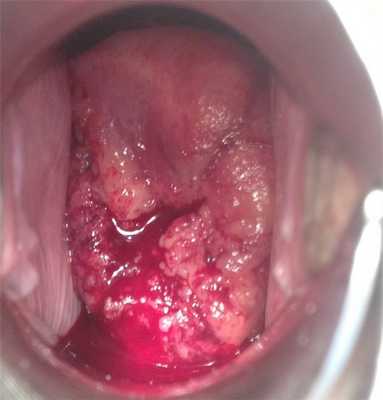

- Осмотр шейки матки в зеркалах. Визуальный гинекологический осмотр в ранней стадии позволяет обнаружить или заподозрить РШМ по внешнем признакам: изъязвлениям, изменению окраски шейки матки. В инвазивной стадии при экзофитном типе роста рака на поверхности шейки матки определяются фибринозные наложения, опухолевидные разрастания красноватого, белесоватого, розовато-серого цвета, которые легко кровоточат при прикосновении. В случае эндофитного роста цервикального рака шейка становится увеличенной, приобретает бочковидную форму, неровную бугристую поверхность, неравномерную розово-мраморную окраску. При ректо-вагинальном исследовании в параметрии и малом тазу могут определяться инфильтраты.

Рис. 2 Опухоль шейки матки